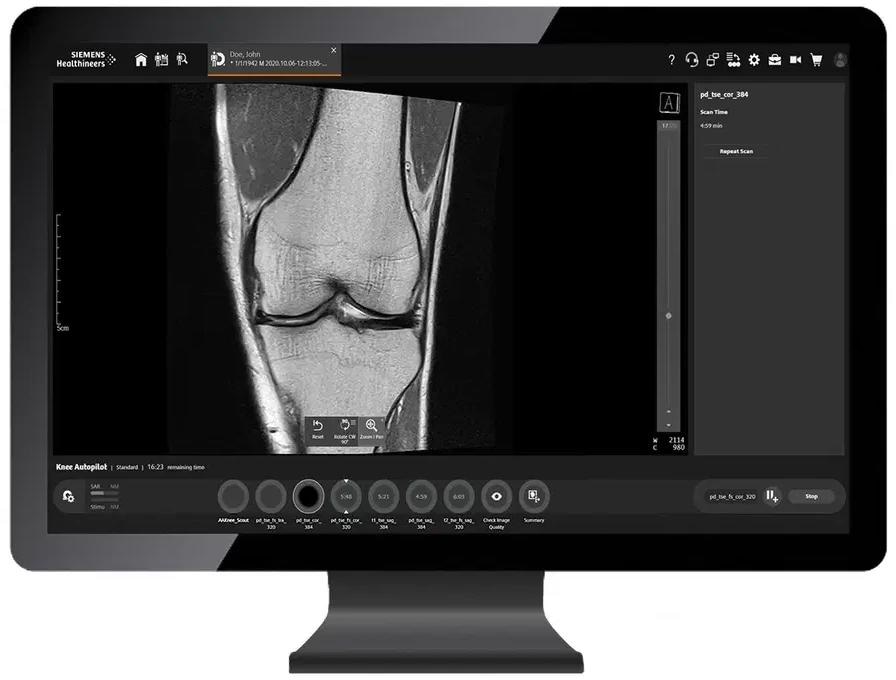

myExam Autopilot

myExam Autopilot offers users the most advanced and intelligent automation. It enables users to scan at high quality with just oneclick.

myExam Companion breaks down the barriers of complex MRI operations using a new philosophy when it comes to operating MRI. Moreover, the novel, innovative myExam Autopilot enables healthcare professionals of any skill level to perform routine MRIs.